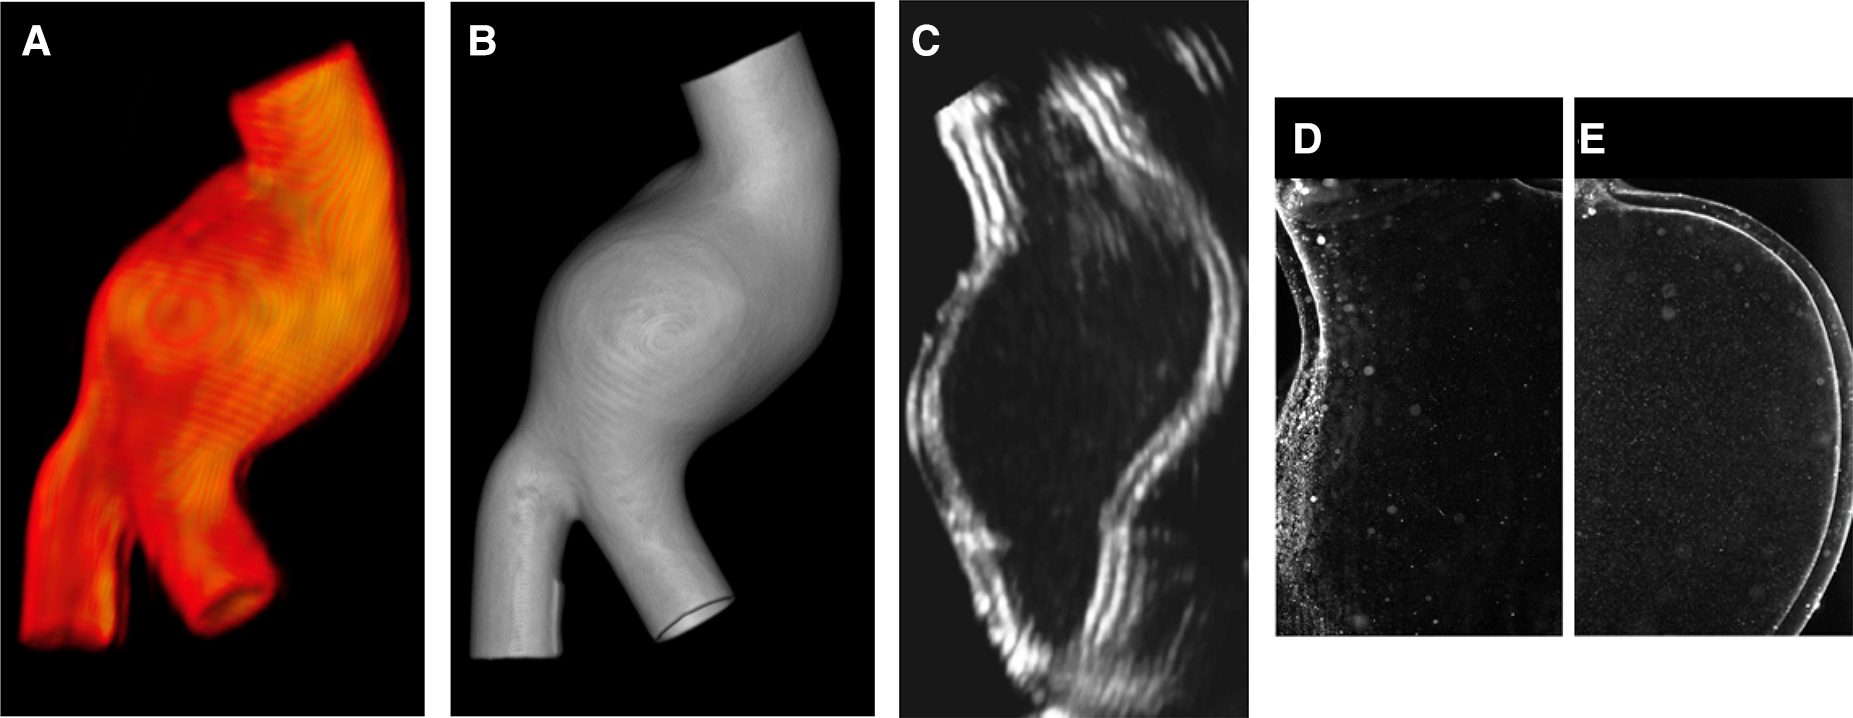

The manufactured model can be inserted into an MCL system to replicate patient-specific hemodynamic conditions and/or perform PIV investigations. In this case, models are often filled with a blood-mimicking fluid and placed within a purpose-designed box, which may then be filled with water, the same blood-mimicking fluid (in PIV), or gelatin (in US imaging). Figures 9A,B shows LMM immersed in water and a blood-mimicking fluid (mixture of water, glycerol, and urea) that matches the refractive index of Sylgard 184. In the latter case, the models become transparent.

Figure 9

LMM filled with water (A) and with a blood-mimicking fluid (B).

As reported in Table 3, the models are also compatible with the main medical imaging modalities. Examples of 3D rendering of MRI and CT scans acquired on the LMM are shown in Figures 10A,B, respectively. An example of Doppler B-mode acquisition of the same model in longitudinal view is depicted in Figure 10C. Finally, an example of illuminated particles for PIV is shown in Figures 10D,E. Portions proximal to LMM’s inlet were illuminated to reveal no particle distortion and no light scattering at the solid/liquid interface.

Figure 10

Render of MRI (A) and CT (B) scans acquired on LMM; B-mode Doppler acquisition in longitudinal view (C); PIV images (D–E).